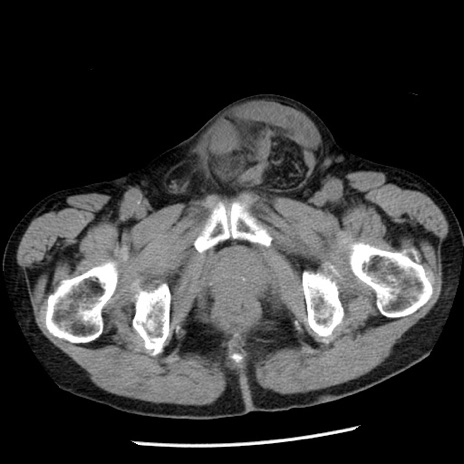

症例26(横断像)

【症例】80歳代男性

【主訴】嘔吐

【現病歴】昨晩2回嘔吐あり、今朝になっても嘔吐あり。来院。

【既往歴】胃潰瘍

【身体所見】意識清明、BT 37.6℃、BP 166/95mmHg、HR 100bpm、SpO2 97%、腹部:平坦・軟、腸蠕動音聴取良好、圧痛なし。

【データ】WBC 21900、CRP 1.46